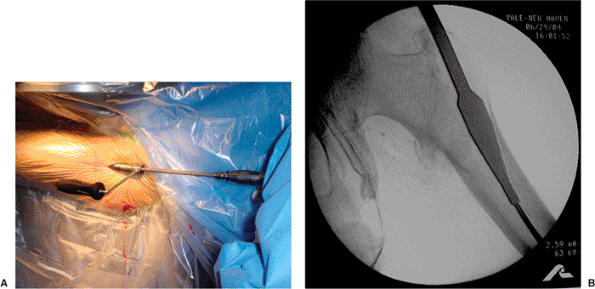

milliliters of local anesthetic with epinephrine proximal to the

greater trochanter. We then make a 2 cm incision and cut down with a

no. 10 blade along the guide pin, through fascia, and directly onto the

greater trochanter (Fig. 17.9).